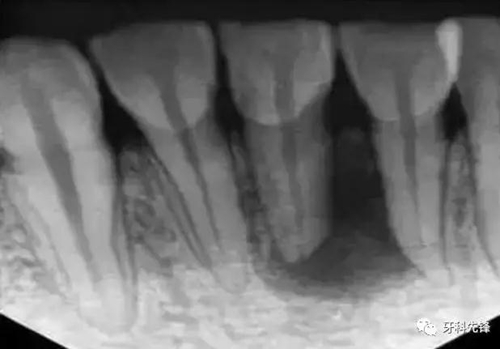

1、術(shù)前拍攝X線片

在根管治療過程中,在根管治療術(shù)前拍X線片,以幫助診斷,了解髓室的位置和根管數(shù)目及形態(tài),測量根管工作長度及日后隨訪和評價(jià)療效提供對比的依據(jù)。